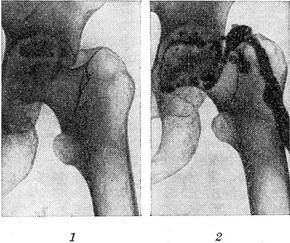

Хронический гнойный коксит, осложнившийся некрозом части головки бедренной кости и образованием свища: 1 — контрольнаярентгенограмма (до фистулографии); 2 — фистулограмма.

Фистулография — методика рентгенологического исследования свищевых ходов путем заполнения их контрастным веществом с последующей рентгенографией (рис.). Основной задачей фистулографии является детальное изучение характера и направления свищевых ходов и их разветвлений, а также установление наличия или отсутствия связи между свищевыми ходами и очагами деструкции (в частности в костях) и инородными телами,секвестрами, абсцессами и другими полостями, расположенными в соседних со свищевым ходом органах. Контрастноерентгенологическое исследование полости абсцесса называется абсцессографией.